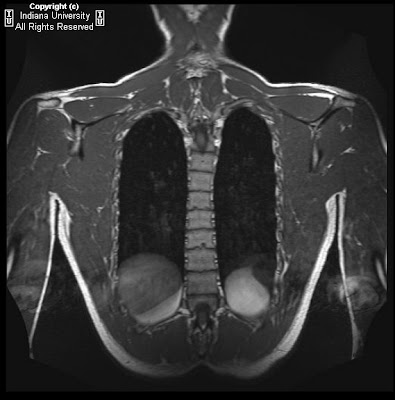

Scheuermann's Disease Schmorl's Node - This Patient With T11/12 Disc Herniation Has Multiple Schmorl's Nodes... | Download Scientific ...

Scheuermann's Disease Schmorl's Node , Schmorl's Nodes (Each Marked By A White Asterisk) Are Seen As Multiple Areas Where Disk Material Extrudes Through The Endplate In The Lumbar Region.